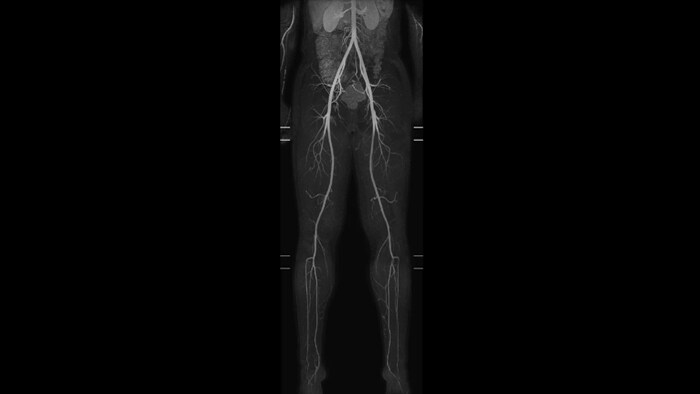

mDIXON XD MultiStation

Clinical application mDIXON XD MultiStation

Vascular Whole Body